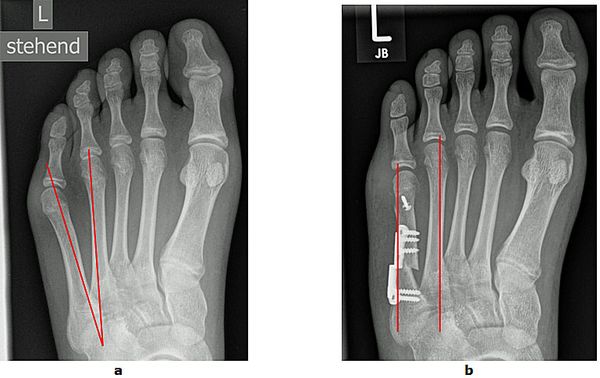

Abb.3: a Korrektur einer mittelschweren Hallux valgus Fehlstellung durch eine Basisosteotomie.

b Korrektur einer schweren Hallux valgus Fehlstellung mit luxierten Krallenzehen und chronischer Metatarsalgie durch eine Lapidus Arthrodese. Mit dieser Technik können selbst hochgradige Fehlstellungen begradigt werden. Bei beiden Techniken wird der Knochen wird mit einer winkelstabilen Platte fixiert. Dies bietet ein höchstes Maß an Stabilität und ermöglicht die sofortige postoperative Belastung.